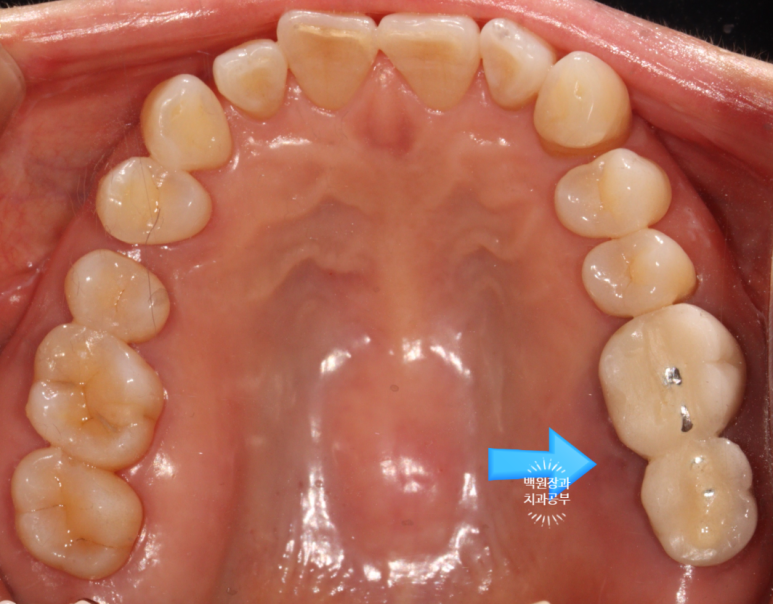

3개월의 치유기간을 가진 후 보시는 바와 같이 새로이 보철물을 제작해 드렸습니다.

약간 이상적이지 않은 형태 같아 보이실 수 있지만!?

입안에서 본 사진 상에서는 상당히 이상적인 지르코니아 크라운 형태로

제작이 잘 되었다는 것 !!